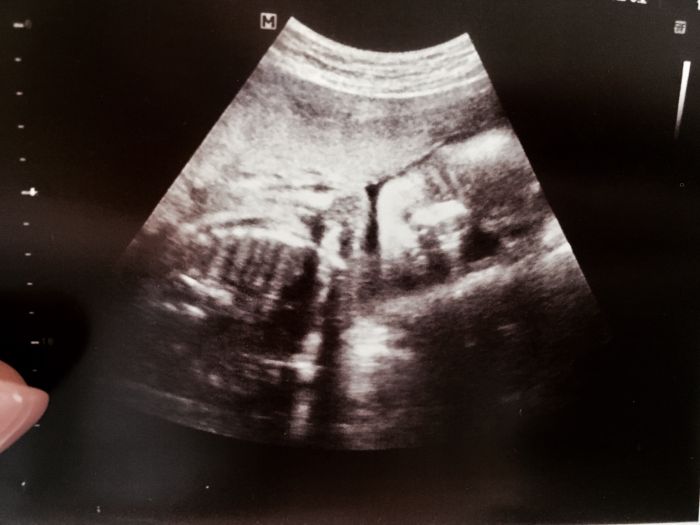

Ahojky holky, ja vás čtu, ale nepíšu. Párkrát jsem napsala na zacatku. :) jinak ja také přemýšlím jak to bude pak s malým. Přecejen mu bude teprve 22mesicu až to přijde. Je na mě hodně zvyklý. Ale zároveň docela kliďas, tatínka chci u porodu, tak budou hlídat babičky nejak. Musíme to vymyslet :) jinak vy co jste po druhé a více těhotné, vidíte to rozdílně? Já se v prvním těhotenství cítila tak krásná a celá jsem zářila :D bříško malinké, teď mam břicho jak předtim v posledním měsíci, nohy oteklý, kolikrát i obličej, prsa obrovský, bolest všeho, takze na procházkách trpím. Bolí mě děsně trisla a v kříži, to jsem měla taky až poslední měsíc v prvním. No je to teď masakr. Do toho litat kolem malého :) je to úplně o něčem jiném. Test na cukrovku mam taky za sebou, mě děla problém vylézt z baráku bez snídaně, jsem zvykla se do 20ti minut od probuzení najíst , takze mi bylo zle z hladu, ale to pití mi nevadilo. Spíš naopak. Konečně jsem do sebe mohla něco dostat :D výsledky OK. Jméno je jedna velká otázka. Nejspíš čekáme podle všeho dalšího kluka. Líbí Se nam Kristianek, ale nevím. Furt přemýšlíme dal. Už máme doma Matyáška. Pro holčičku jsem nejak nepřemýšlela, ale když byl jasně vidět na UTZ pinďourek, tak už se z toho holcicka snad nestane ne? :D :) Těhotenské oblečeni nemám, nosím leginy , jedny kalhoty a nejak mi to nevadí. Alorat by mohlo už začít být teplo, v tomhle měsíci jsem v prvním těhotenství už nosila šaty a v těch mi bylo nejlépe , tak bych je taky už docela ráda vytáhla :) dávám foto pupíku a posledního UTZ.